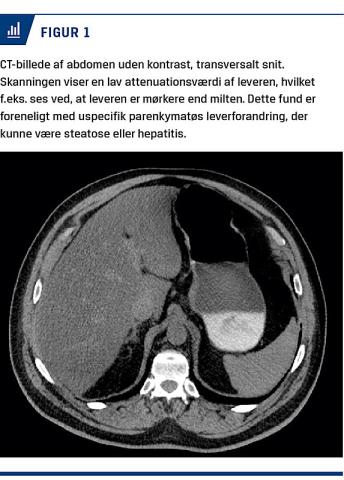

Under indlæggelse på intensiv og nefrologisk afdeling blev han fundet negativ for: Hantavirus, leptospirose, hepatitis A, B og C samt salicylat- og paracetamoloverdosering. Ligeledes blev han screenet negativ for antinukleære antistoffer, antineutrofile cytoplasmatiske antistoffer, mitokondrieantistof, glat muskulatur-antistof, glomerulær basalmembran-antistof, mitokondrie (E3-subunit)-immunglobulin G, M-komponent og aktin-AB. Undervejs blev der ved CT fundet pneumonisk udseende infiltrater i lungerne og uspecifikke parenkymatøse forandringer i leveren (Figur 1).

Man kunne ikke finde nogen sikker årsag til nyre- og leverpåvirkningerne hos patienten i sygehistorien. Ser man på litteraturen om røde gærris, fremstår indtaget heraf dog som en sandsynlig årsag. Monacolin K er flere gange beskrevet som formodet årsag til rabdomyolyse lig andre statiner. Ydermere er der beskrevet mere end ti tilfælde af hepatitis og transaminaseforhøjelse og sågar et enkelt tilfælde af svær lobulær levernekrose [2]. Denne sygehistorie lægger sig således i kølvandet på disse tilfælde, med sin rabdomyolyse og ALAT-forhøjelse, hvor den påviste parenkymatøse reaktion af leveren kunne være en følge af røde gærris-induceret hepatitis.